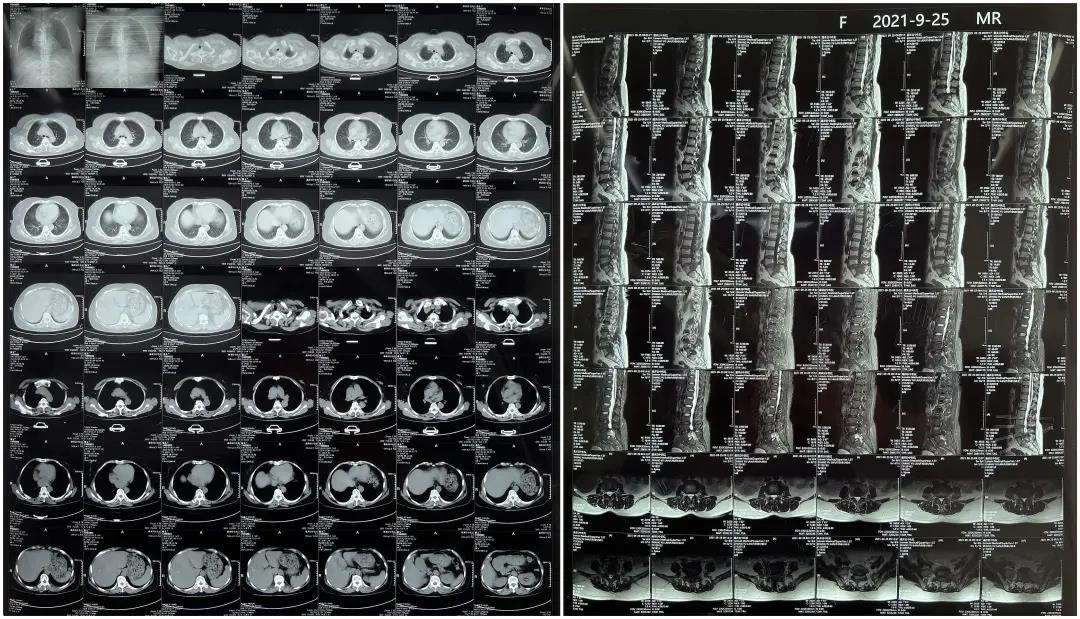

患者1:女性,56歲,L5/S1椎間盤椎板減壓+釘棒固定術(shù)

患者下腰部疼痛,活動受限,伴有左下肢疼痛5年,久站或彎腰干活時疼痛加劇,臥床休息后疼痛癥狀緩解,近一個月情況加重,需行椎板減壓+釘棒固定術(shù)。

術(shù)前患者核磁共振圖像

顯示L3/4、L4/5椎間盤突出,L5-S1水平椎管內(nèi)占位